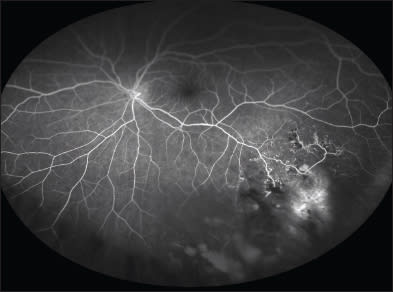

Figure 6. A dramatic widefield angiogram of a patient with sickle cell disease and neovascularization with no posteriorpole findings (imaged with the Optos 200 Tx).

The benefit of using widefield angiography for the evaluation and management of sickle cell retinopathy was described by Cho in 2011.32 In that sickle disease can cause dramatic peripheral changes that can lead to vitreous hemorrhage and retinal detachment, using widefield angiography to complement examinations in identifying and treating at-risk patients could have important clinical implications (Figure 6).

Similar to diabetes and vein occlusions, almost all retinal vascular disease may benefit from imaging of the peripheral retina. Certain retinal vascular diseases, such as sickle cell retinopathy and Coats disease, usually demonstrate peripheral pathology that may be missed entirely by only imaging the posterior pole.